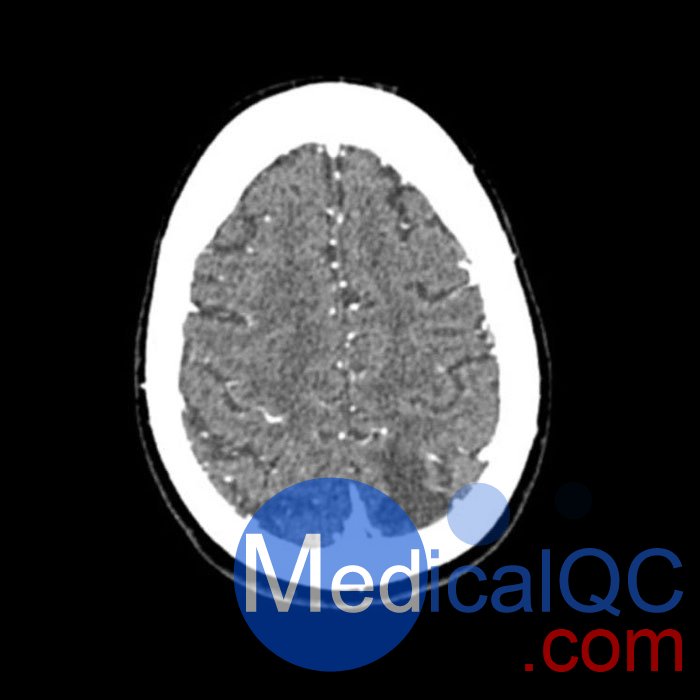

WEK50-03動脈瘤頭模,WEK50-03血管造影CTA頭模是頭部 CTA 動脈瘤模型

模擬造影劑動脈期頭部增強(CT血管造影)。 它覆蓋了頂點枕骨大孔。

模型有三個顱內(nèi)動脈瘤

大腦中動脈 (MCA) 的前部

交通動脈 (ACoA) 和基底動脈動脈。

該體模可用于CT(包括CBCT)評估和優(yōu)化成像性能和人工智能診斷。 這是也適合培訓目的。

模型提供了詳細且真實的模擬常見的大腦病理,軟和骨組織。 空氣空隙充滿了約的纖維素聚合物復合材料 -160HU。

WEK50-03動脈瘤頭模,WEK50-03血管造影CTA頭模影像圖:

更多效果和DICOM數(shù)據(jù)請聯(lián)系我們